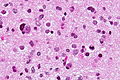

Microscopic

Features:

- Ganglion-like cells with a prominent nucleolus.

- Small undifferentiated cells with scant cytoplasm.

Images: